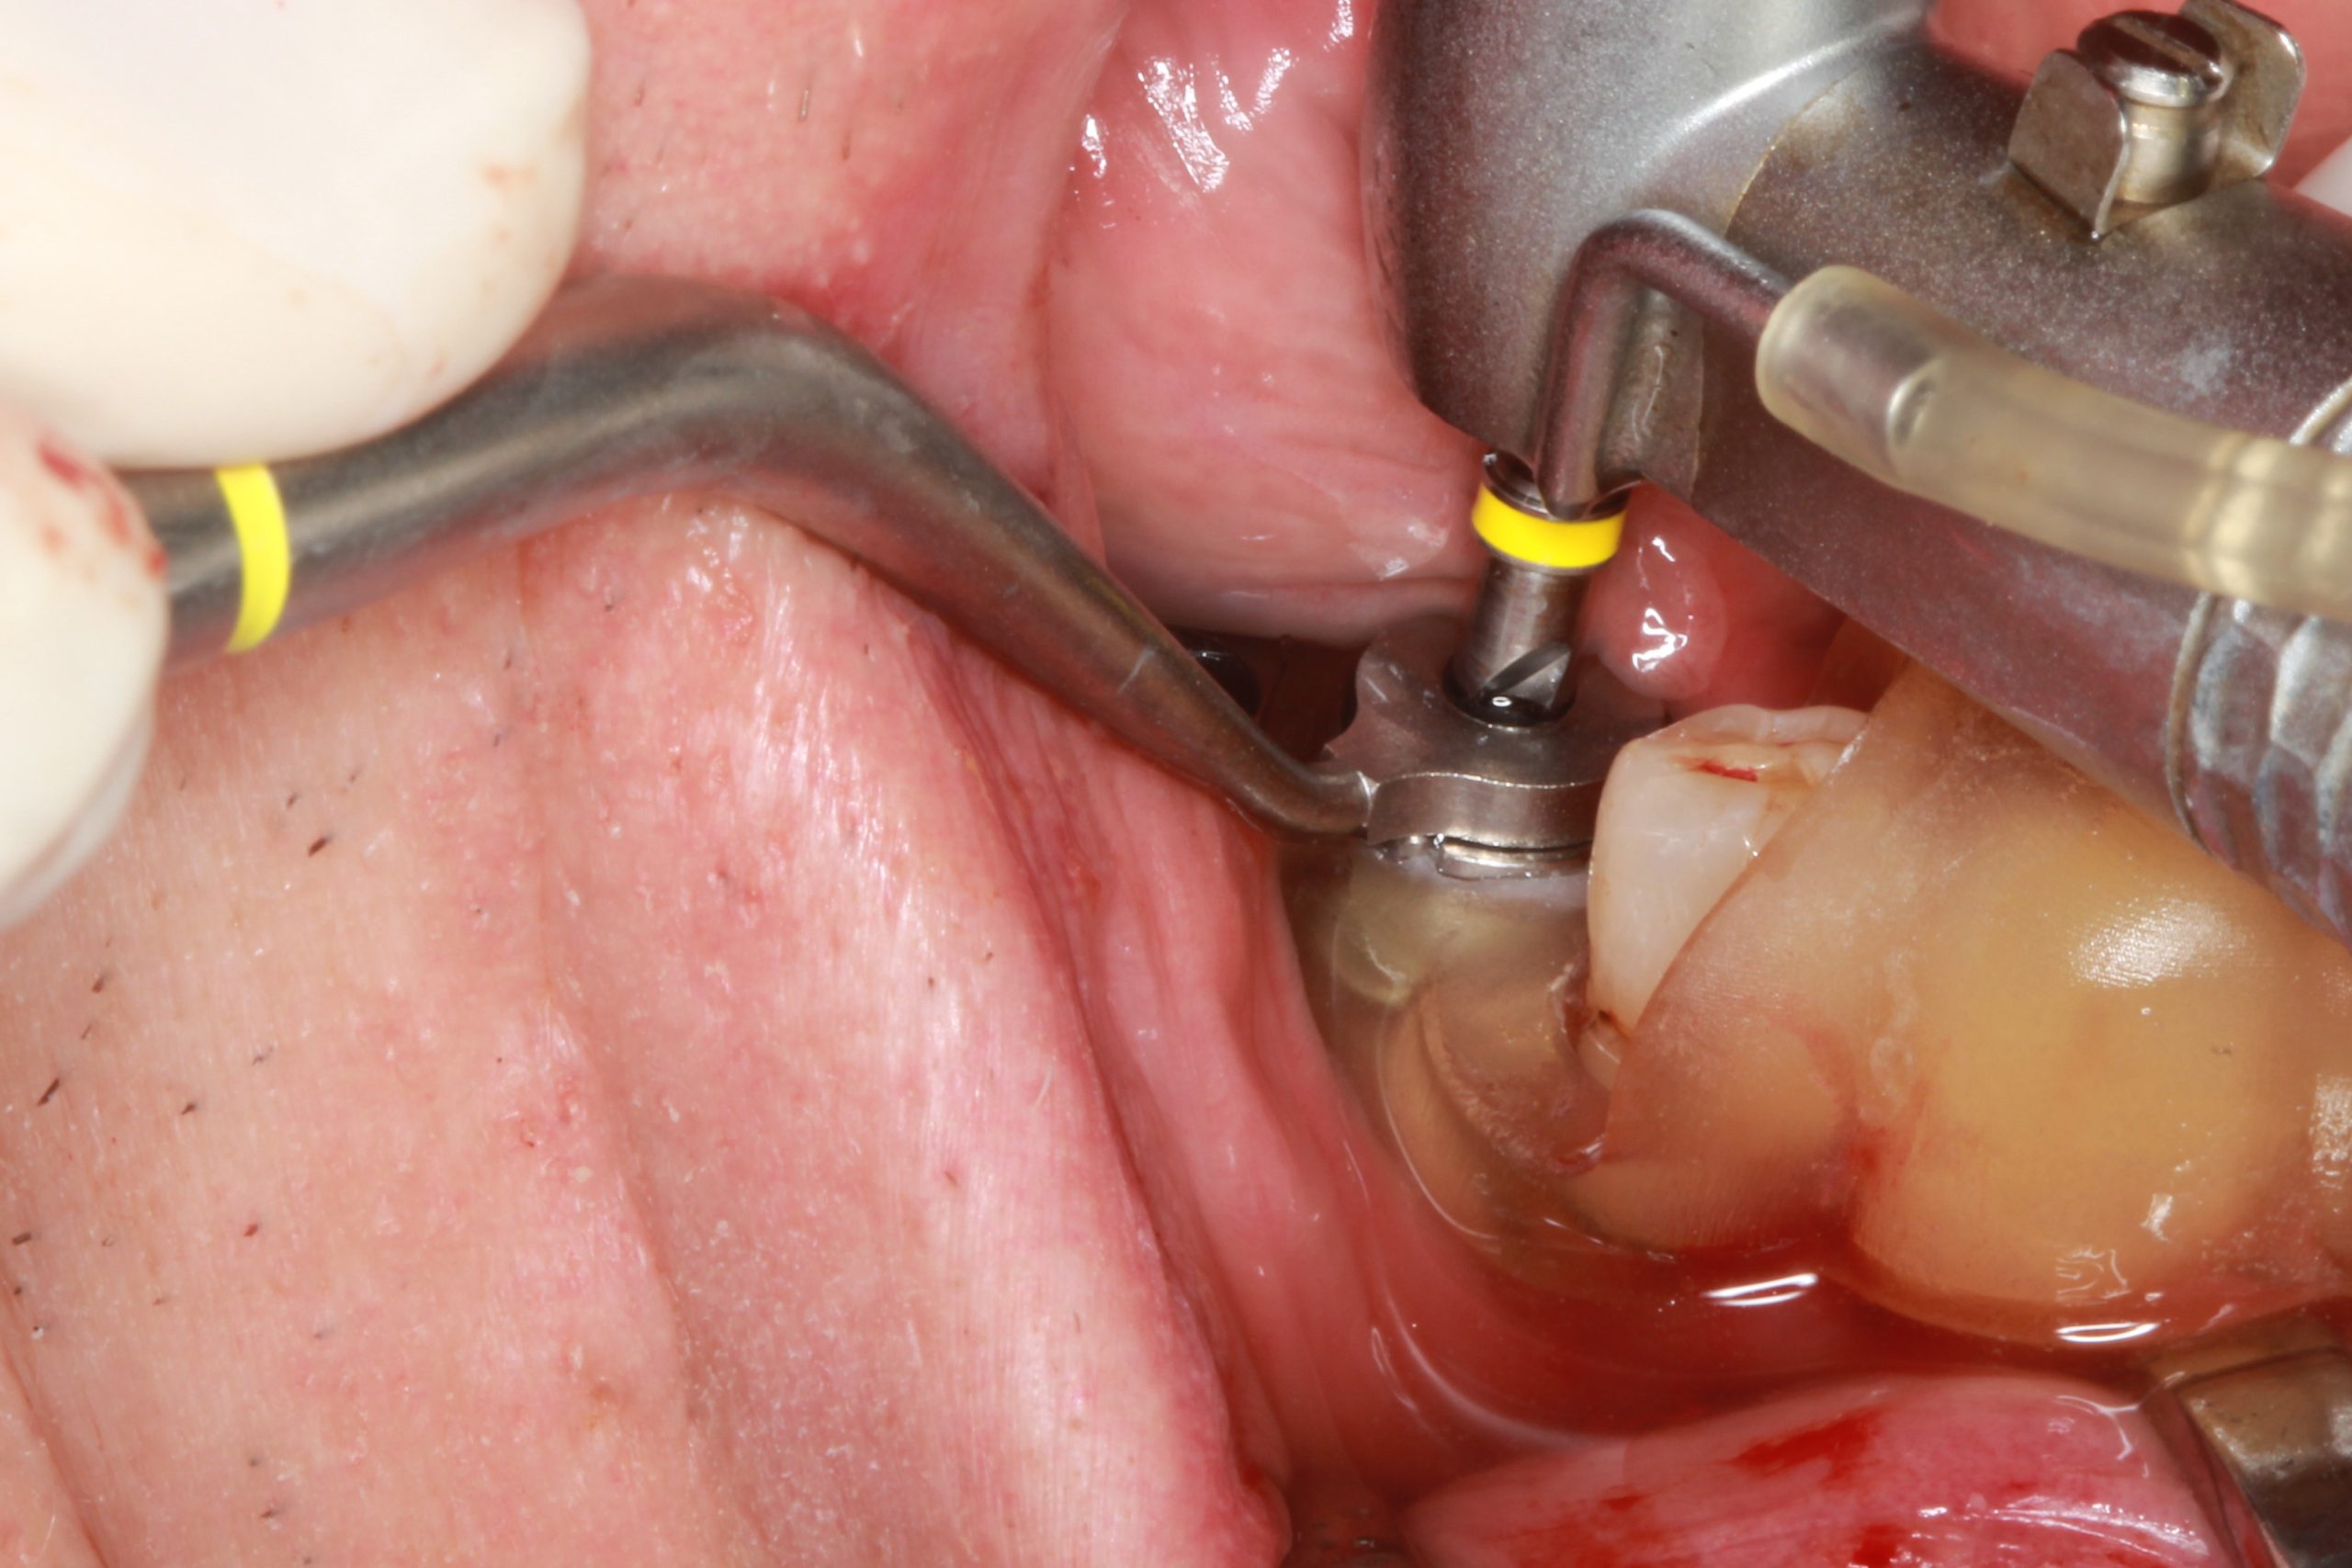

In accordance with the surgical protocol, the S2.9 guided drill with the required length and an S2.9 drill guide (with the same color strip) of the smallest diameter of 2.3 mm were used.

Then the treatment was continued with the drills and the drill guides for the appropriate implant diameter.

The preparation was completed using guided countersinks and threadformers with C-guides. After the surgical template was removed, the implant was placed.